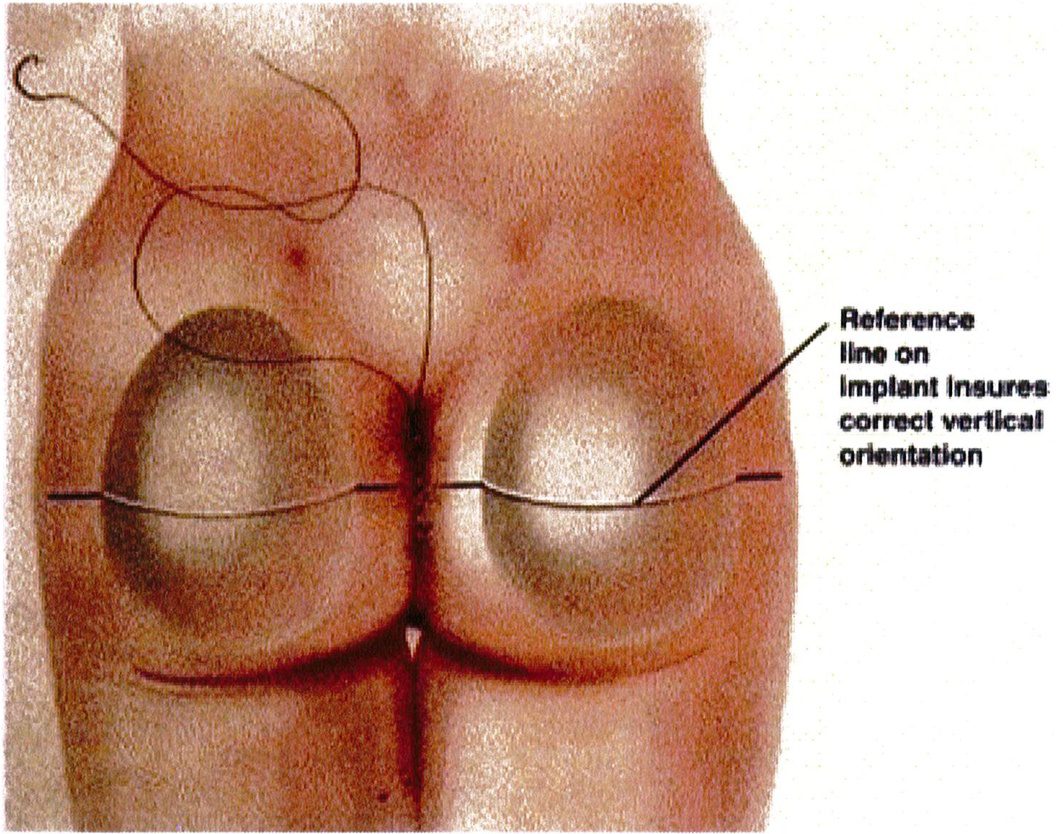

Sau đó, mô cấy sẽ được đưa vào, đảm bảo rằng nó được căn chỉnh hoàn hảo, thẳng trục và vừa khít bên trong túi (Hình 15). Chúng tôi nhấn mạnh rằng tất cả các khối implant đều phải có 1 đường trắng chạy ngang qua tâm điểm của chúng để tạo thuận cho việc căn chỉnh vị trí (Hình 16). Không bao giờ được đặt khối implant chếch vì chúng sẽ tạo ra hiệu ứng bong bóng kép ở ¼ dưới ngoài vùng mông (Hình 17).

Hình. 15. Đường chia đôi mông theo phương ngang phải đi qua đường trắng giữa của khối implant để đảm bảo khối này được đặt đúng vị trí.

Hình. 16. Hình nhìn từ phía sau các khối implant ở đúng vị trí trong mối tương quan giữa xương cùng, rãnh liên mông và giới hạn ngoài cơ mông lớn. Đường giữa được vẽ nét liên trên hình đi qua cả hai đường đánh dấu của khối implant. (Trích từ de la Pena JA. Subfas -cial technique for Gluteal Augmentation. Aesthet Surg J 2004;24:269. đã xin phép trước khi đăng tải.)